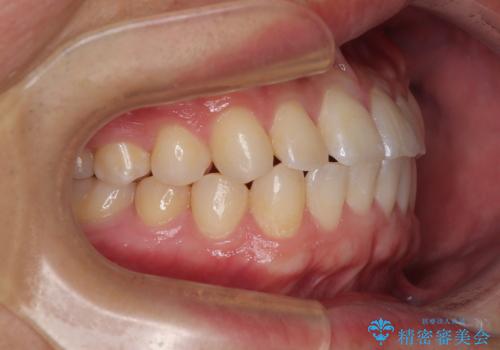

前歯のガタガタ・奥歯のかみ合わせ(シザーズバイト)を改善|1年半で完了したメタルブラケット矯正

今回ご紹介するのは、「前歯のガタガタ(叢生)」と「奥歯のかみ合わせ(シザーズバイト)」にお悩みでご来院された患者様の症例です。

▼ 診断

・上顎左右の第二大臼歯が頬側へ転移し、シザーズバイト(scissors bite)の状態

・上顎左側第二小臼歯が90度捻転しており、噛み合わせに影響